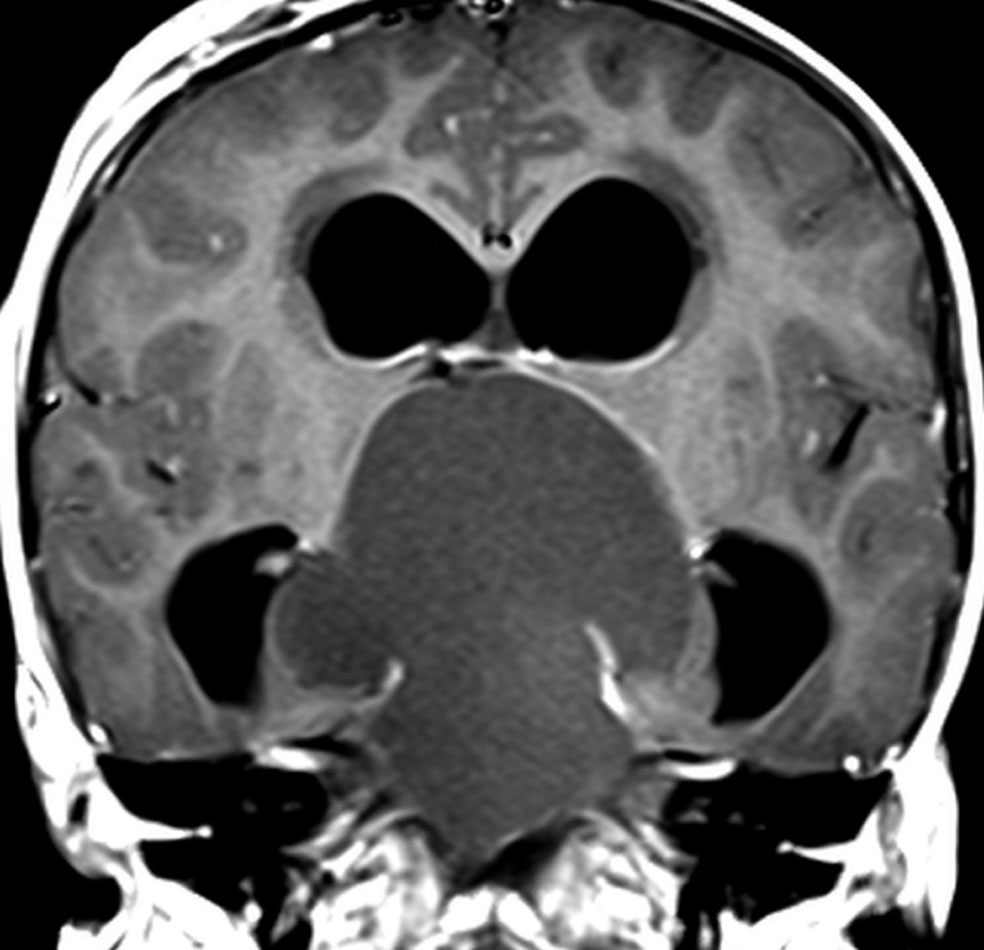

この子の症状は頭痛だけ。両親はなぜ気づかなかったのかと疑問を持ちますが,巨大になるまで症状が出ないこともあるのです。左のCTで腫瘍の周囲にバラバラと白い点状の石灰化があるので診断できます。左の視床下部から発生したクラニオでした。開頭手術しますが超高難易度です,怖いです (┯_┯) 複数回開頭手術になりましたが結果的に全摘出できています (by Dr 山本哲哉)。

ちょっと大きな頭蓋咽頭腫です

嚢胞(液体が入っている袋)の部分と,腫瘍細胞が固まっている実質部分が入り交じっています。このくらいの大きさになってしまうと,下垂体機能を残すことはとても難しくなります。視神経が圧迫されて視力低下と視野障害を生じます。第3脳室が腫瘍で閉塞していて水頭症になっていますから知能の活動が低下します。

腫瘍を摘出するのに危ないのは,脳の血管の損傷です。左では白く,右では黒く線状に移っているのが太い脳動脈です。これら以外にもたくさんの細い重要な動脈が絡んでいます。

幸いこの患者さんの腫瘍は摘出できて患者さんは元気になりました。でもこのくらいのサイズになると手術がいつもうまくいくとは限りませんし重大な障害が残ることもあります。